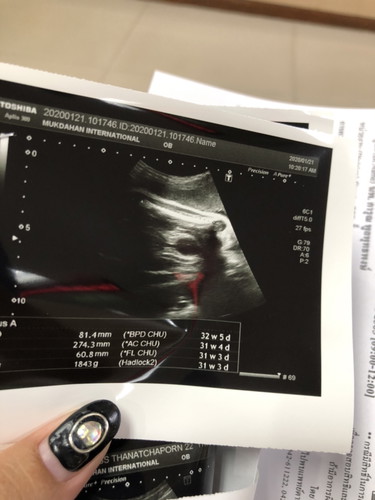

31+4 ????

บ้านนี้ น้ำหนัก1843gโดยประมาณ บ้านอื่นอายุครรภ์เท่ากัน นน เท่าไหร่กันบ้างแล้วค่ะ

บ้านนี้ตอน 31+5 อยู่ที่ 1,9xx กำลังจะแตะ 2 พันจ้า